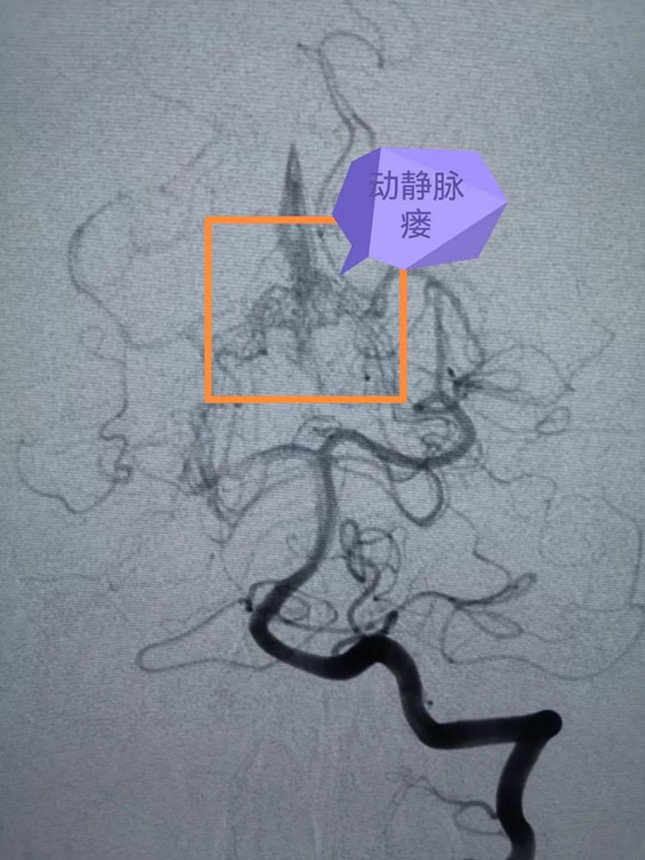

但是脑血管疾病种类较多,形态多样,头颅MR仍然无法进一步确诊,诊断脑血管疾病的“金标准”则是全脑血管造影(DSA),海西州人民医院此前已经具备了此项特殊检查的硬件设施和人员配备。巴特尔副主任医师更是在2年前就在浙大一院进修学习掌握了全脑血管造影技术。于是,他随后即带领海西州人民医院的本土团队为大梅顺利开展了全脑血管造影术,术中发现大梅的小脑幕区贴近脑干处,有个直径约1cm、像蚯蚓一样扭曲的脑血管畸形。

▲术前DSA影像

面对远道而来的浙大一院神经外科专家,患者和家属喜极而泣,并表示了无条件的信赖。10月17日,克服着高原反应的潘剑威主任医师、严敏主治医师和巴特尔副主任医师一起在海西州人民医院成功为大梅进行了“复杂型脑血管畸形栓塞术”。此时大梅不仅脑干出血,脑部的血管畸形团块由大量细小的动静脉瘘组成,动脉血直接进入静脉,迂曲扩张的静脉在动脉血流的冲击下非常容易再次破裂出血,形成脑内血肿危及生命,手术迫在眉睫。